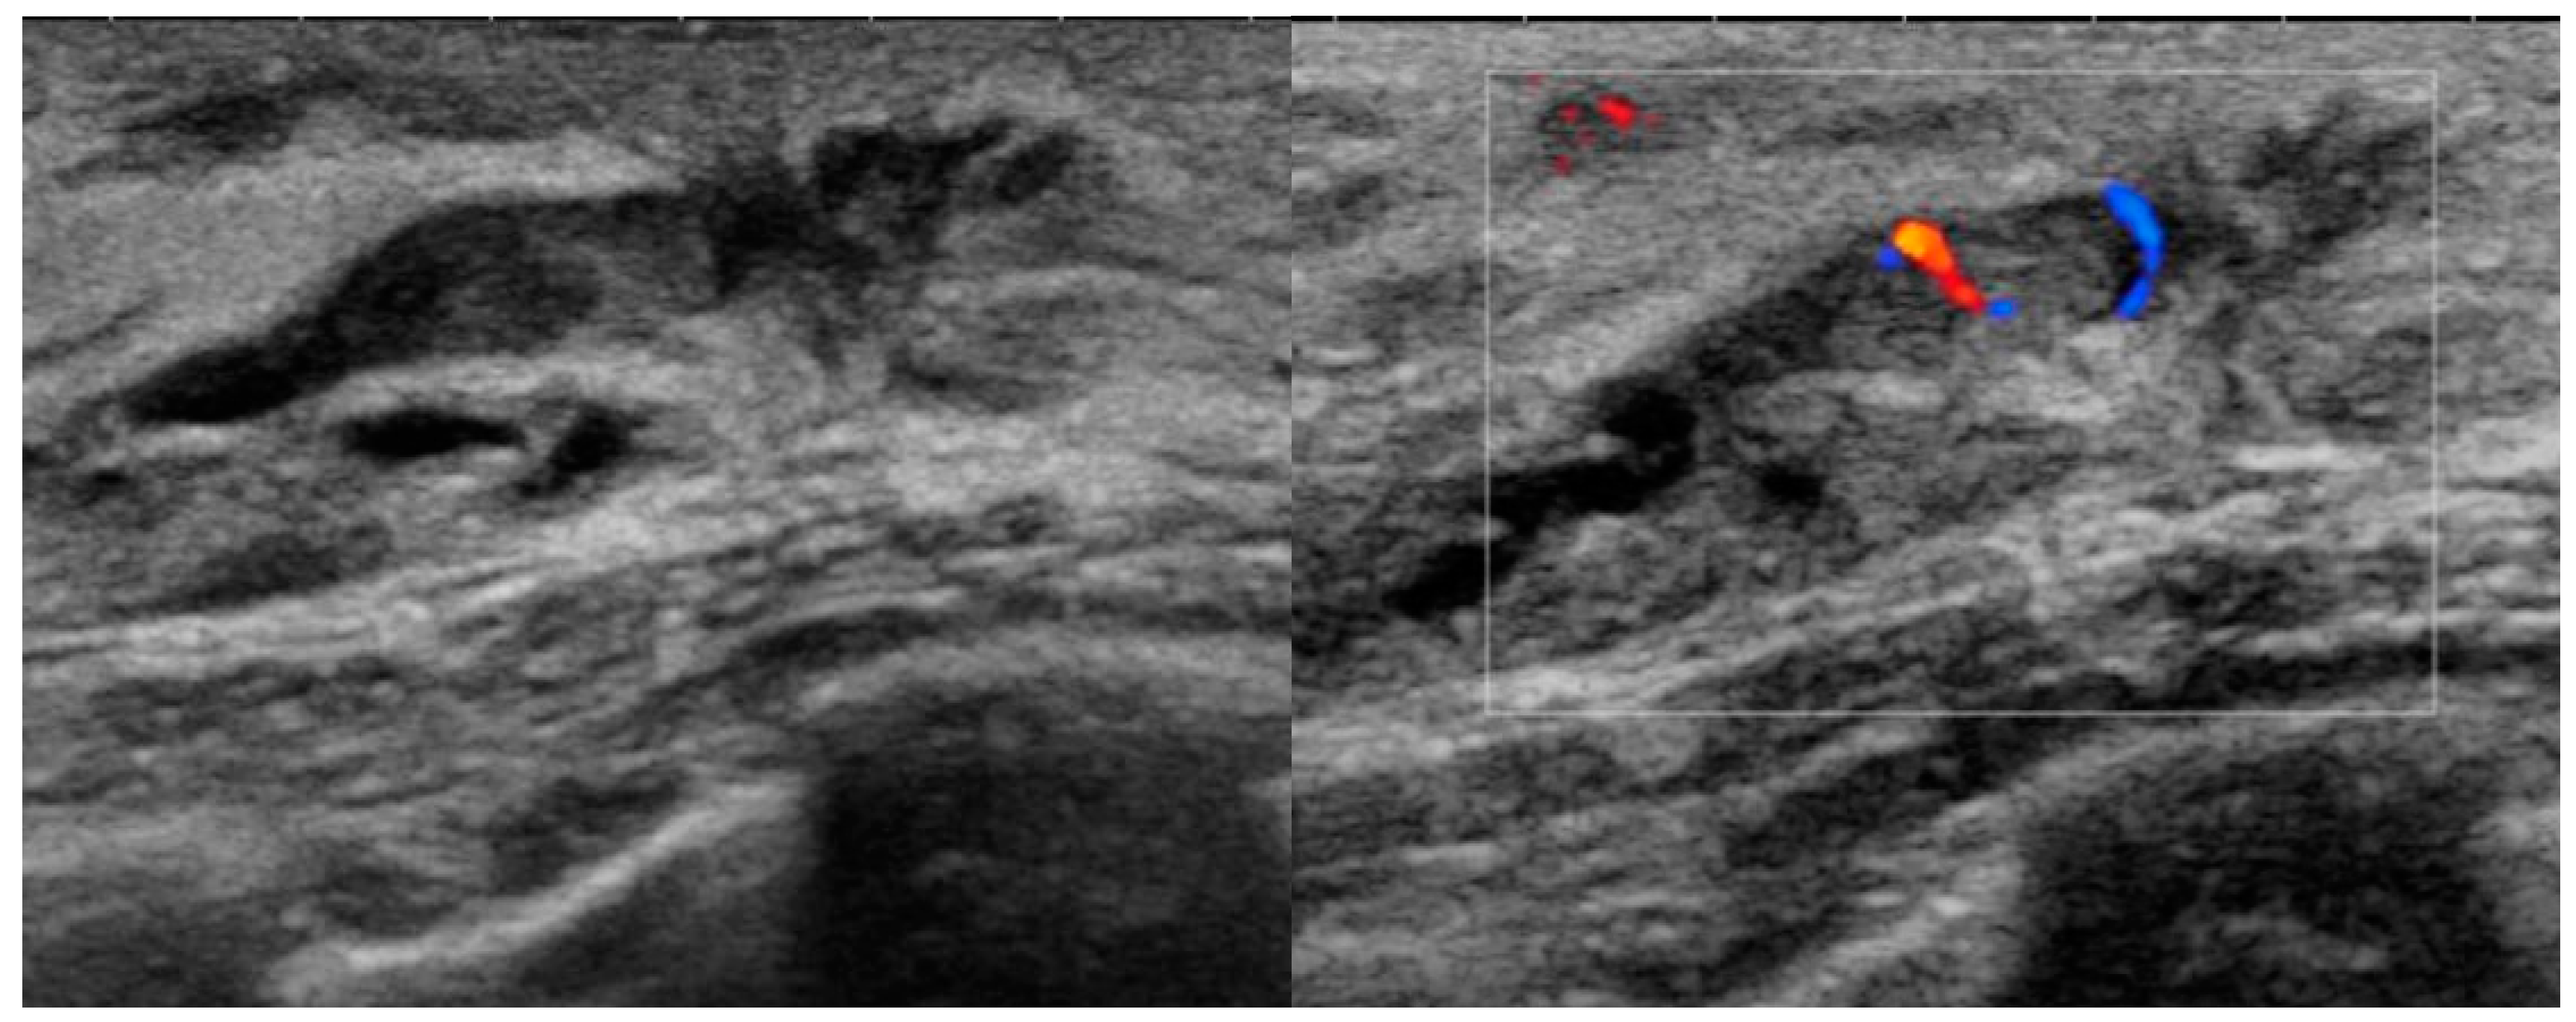

| Ductal change on US (n) (−) (+) | 55 13 (23.6%) 42 (76.4%) | 240 167 (69.6%) 73 (30.4%) | <0.001 |

| Intraductal feature on US (n) (−) (+) | 55 15 (27.3%) 40 (72.7%) | 240 171 (71.3%) 69 (28.8%) | <0.001 |